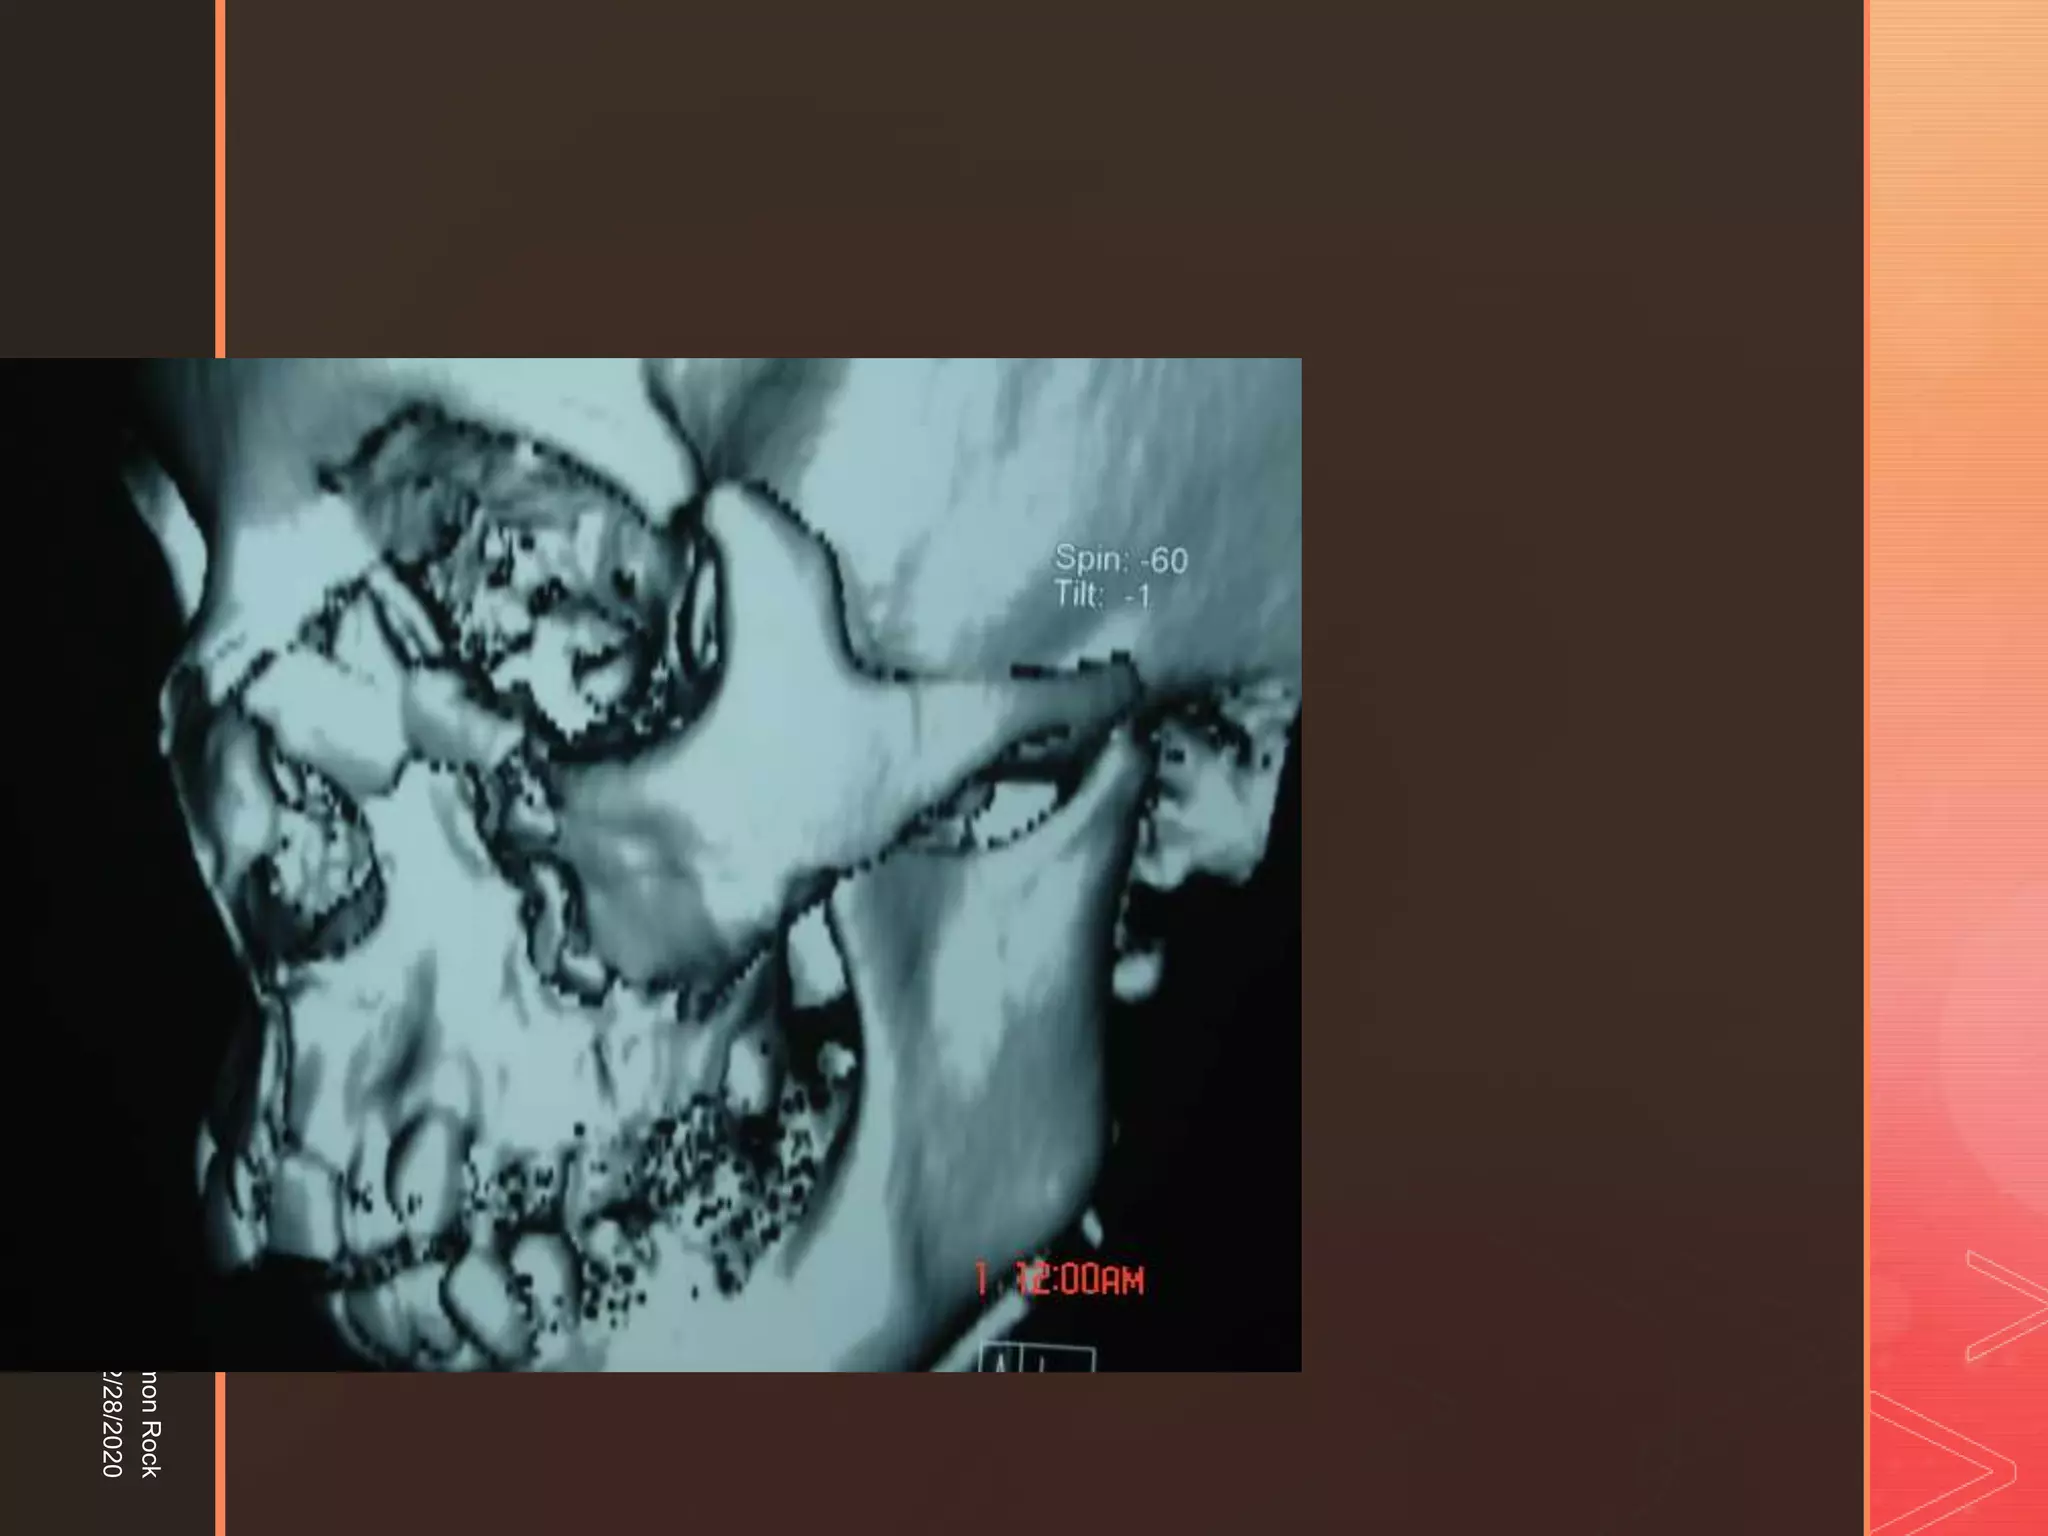

This document discusses the anatomy and fractures of the zygomatic bone. It notes that the zygoma forms the cheekbone and articulates with several other facial bones. Zygomatic fractures most commonly occur in the arch or body due to blunt trauma. Diagnosis involves checking for diplopia, ecchymosis, and other signs of orbital or facial bone involvement. Treatment may involve closed or open reduction based on the severity of displacement. Closed reduction techniques try to elevate the bone back into position without surgery, while open reduction requires surgical exposure and fixation of the fracture site.